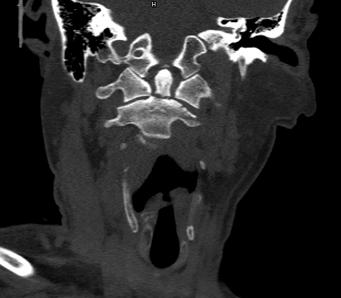

近日,45岁的王先生因高处坠落伤致颈部疼痛、活动受限,于是到北京友谊医院就诊。结合CT结果,医生诊断王先生为枢椎齿状突II型骨折,需手术治疗,王先生被收入骨科病房。

辅助检查显示:颈椎前部可及多发血肿,枢椎齿状突骨折部位向后方移位。